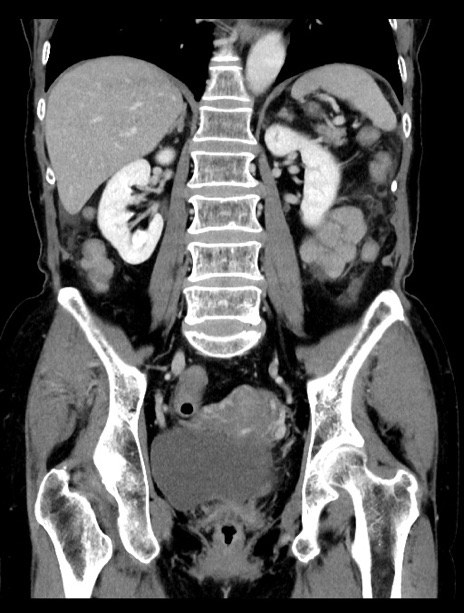

症例23(冠状断像)

【症例】70歳代女性

【主訴】下腹部痛・嘔吐

【現病歴】2日前より腹痛あり。昨日嘔吐あり。症状改善しないため来院。

【既往歴】胃GISTに対して胃部分切除後。

【身体所見】BT 37.1℃、BP 128/77mmHg、腹部:平坦・軟、下腹部に圧痛あり。

【データ】WBC 10200、CRP 0.31